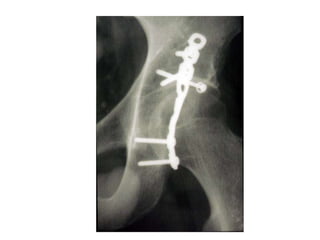

Reconstruction plates

 Deep notches between holes

 Accurate contouring in any

plane

 Pelvis

 Acetabulum

 Distal humerus

 Clavicle

 Olecranon